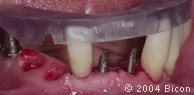

22. | 种植体内径和龈袖口。 |

23. | 种植体内径和龈袖口。 |